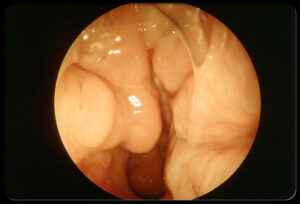

پولیپ های بینی:

وقتی که سینوس ها ملتهب باقی می مانند، پوشش مخاطی سینوس ممکن است ضخیم شده و ورم کنند. این تورم ممکن است آن قدر زیاد باشد که توده های انگور مانندی تولید کند که به آن ها پولیپ می گوییم. پولیپ ها ممکن است از سینوس ها وارد شده و به طور ناقص یا کامل راه هوایی بینی را ببندند.